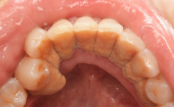

牙石堆积                                         牙龈红肿出血